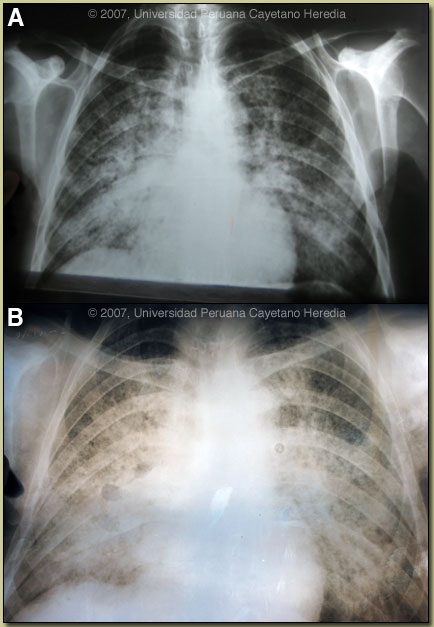

History: 52 year old male who presented with a 4 month history of fever, night sweats, dyspnea, dry cough and a 25 kg weight loss. He also reports increasing hoarseness and increasing pain on swallowing. Initial sputum examination for acid-fast bacilli was negative, but 1 month prior to admission he presented at a hospital in another city and was diagnosed with sputum positive TB [chest X-ray shown in Image A] and begun on standard 4-drug therapy with which he was adherent. At the time of admission he reports continued progression of his symptoms and weight loss.

Epidemiology: Patient is a farmer from Quillabamba in the jungle regions of Cusco Department. Non-smoker, non-drinker, no previous TB history. Was treated with an unknown quantity of antimony 15 years ago for a cutaneous leishmania ulcer on his chest wall. Physical Examination: Afebrile. Normal vital signs. 2 cm non-tender right cervical lymph node. Direct laryngoscopy disclosed a granulomatous appearing lesion on the true vocal cords. Examination of the chest disclosed no evidence of pleural effusion or consolidation. There were bronchial breath sounds bilaterally but worse at the right base. No hepatosplenomegaly. Skin: quiescent psoriasis most marked on the legs, scar of previous leishmanial ulcer. Laboratory Examination: Hematocrit 35. WBC 16.7 with 70 neutrophils, 4 bands, 3 eosinophils, 21 lymphs. LFTs normal. BUN, creatinine normal. HIV negative. HTLV-1 negative. 3 induced sputum samples for acid fast bacilli and PAS staining negative. Chest X-ray soon after admission and after over 1 month of anti-TB medication is shown in Image B. Vocal cord biopsy was positive for Leishmania but as this did not explain the progressive pulmonary disease, a lymph node biopsy was performed. |

We have recently presented a case of mucocutaneous leishmaniasis [Gorgas Case 2006-05] and will not discuss that infection in detail further here, but focus on the pulmonary disesase. The major differential diagnosis in Peru of oro-pharyngeal lesions in non-HIV infected patients would be mucosal leishmaniasis, paracoccidioidomycosis, carcinoma, or lymphoma. In Peru leishmaniasis would be by far the most common. The spread to the larynx and vocal cords is consistent only with leishmaniasis. In general, oral lesions of paracoccidioidomycosis are painful, are frequently friable and bleed on contact, and gingival and buccal mucosa are frequently involved. The differential diagnosis for the lung disease includes: TB, histoplasmosis, lymphoma, cancer and cryptococcosis. The most typical radiographic pattern of paracoccidioidomycosis is bilateral mixed infiltrates (alveolar and interstitial), mainly located in the middle and lower lobes. Interstitial lesions may have a miliary, nodular or fibronodular patterns. Other patterns observed in these patients are hilar and mediastinal lymph node enlargement, cavities, and calcified lesions. Our patient has advanced disease and almost all of these findings on CT scan of the lung [Image D]. Extrapulmonary disease is found in over 70% of cases and may involve skin, mucous membranes, lymph nodes, adrenals, abdominal organs and CNS (in 10%). Bacterial superinfection of ulcerative oral lesions when they occur is more common than with oral ulcers due to mucocutaneous leishmaniasis. This case is representative of the chronic form (adult type) of the disease, which is believed to represent reactivation of latent infection. This type represents approximately 94% of all cases in the experience at our institute (94 patients, up to 2001), and approximately 85% in the Brazilian series [Rev Soc Bras Med Trop. 2003;36(4):455-9]. In our experience the male:female ratio in chronic paracoccidioidomycosis is 20:1. As in this case, TB coexists in up to 10% of patients with paracoccidioidomycosis. Cavitation and pleural effusion are less commonly seen than in TB. The negative acid fast stains during the current hospitalization after 1 month of therapy would not be consistent with MDR TB. Paracoccidioidomycosis, also known as South American blastomycosis is found in humid forested or lush green areas of the Americas from Southern Mexico south to Uruguay and Argentina. It appears to be most common in Brazil. The exact habitat of the organism is unclear but transmission is described as being entirely by airborne inhalation. However, we have observed cases with only oral lesions apparently associated with the use of tree leaves contaminated with fungal spores as toothpicks. Primary pulmonary infection may be asymptomatic and self-limited but even with treatment will produce at least moderate pulmonary fibrosis. Rural adult male agricultural workers between 30-60 years of age are most affected by the infection. Travelers spending less than 6 months in an endemic area are unlikely to acquire paracoccidioidomycosis. Sulfonamides, ketoconazole, itraconazole, and amphotericin B are all effective therapies. Amphotericin should be reserved for severe cases. Itraconazole 100-200 mg/day for 6-9 months is regarded as the treatment of choice when it is available and affordable. Relapses are common with less than 6 months therapy and expert opinion is now that 1 year is not necessary. In the developing-world setting, ketoconazole is likely equally effective and is usually less than half the cost. However, 12 months of therapy with ketoconazole is generally recommended. In severe cases with a high yeast burden such as in our case, the practice is to induce such patients with amphotericin B for at least 10 days, then switch to oral itraconazole 200 mg per day, to complete a total duration of at least 9 months. As amphotericin B for 28 days is the therapy of choice for mucosal leishmaniasis that has developed despite previous treatment of cutaneous disease with antimony, our patient was begun on 0.5 mg/kg per day. The TB therapy is continuing. |